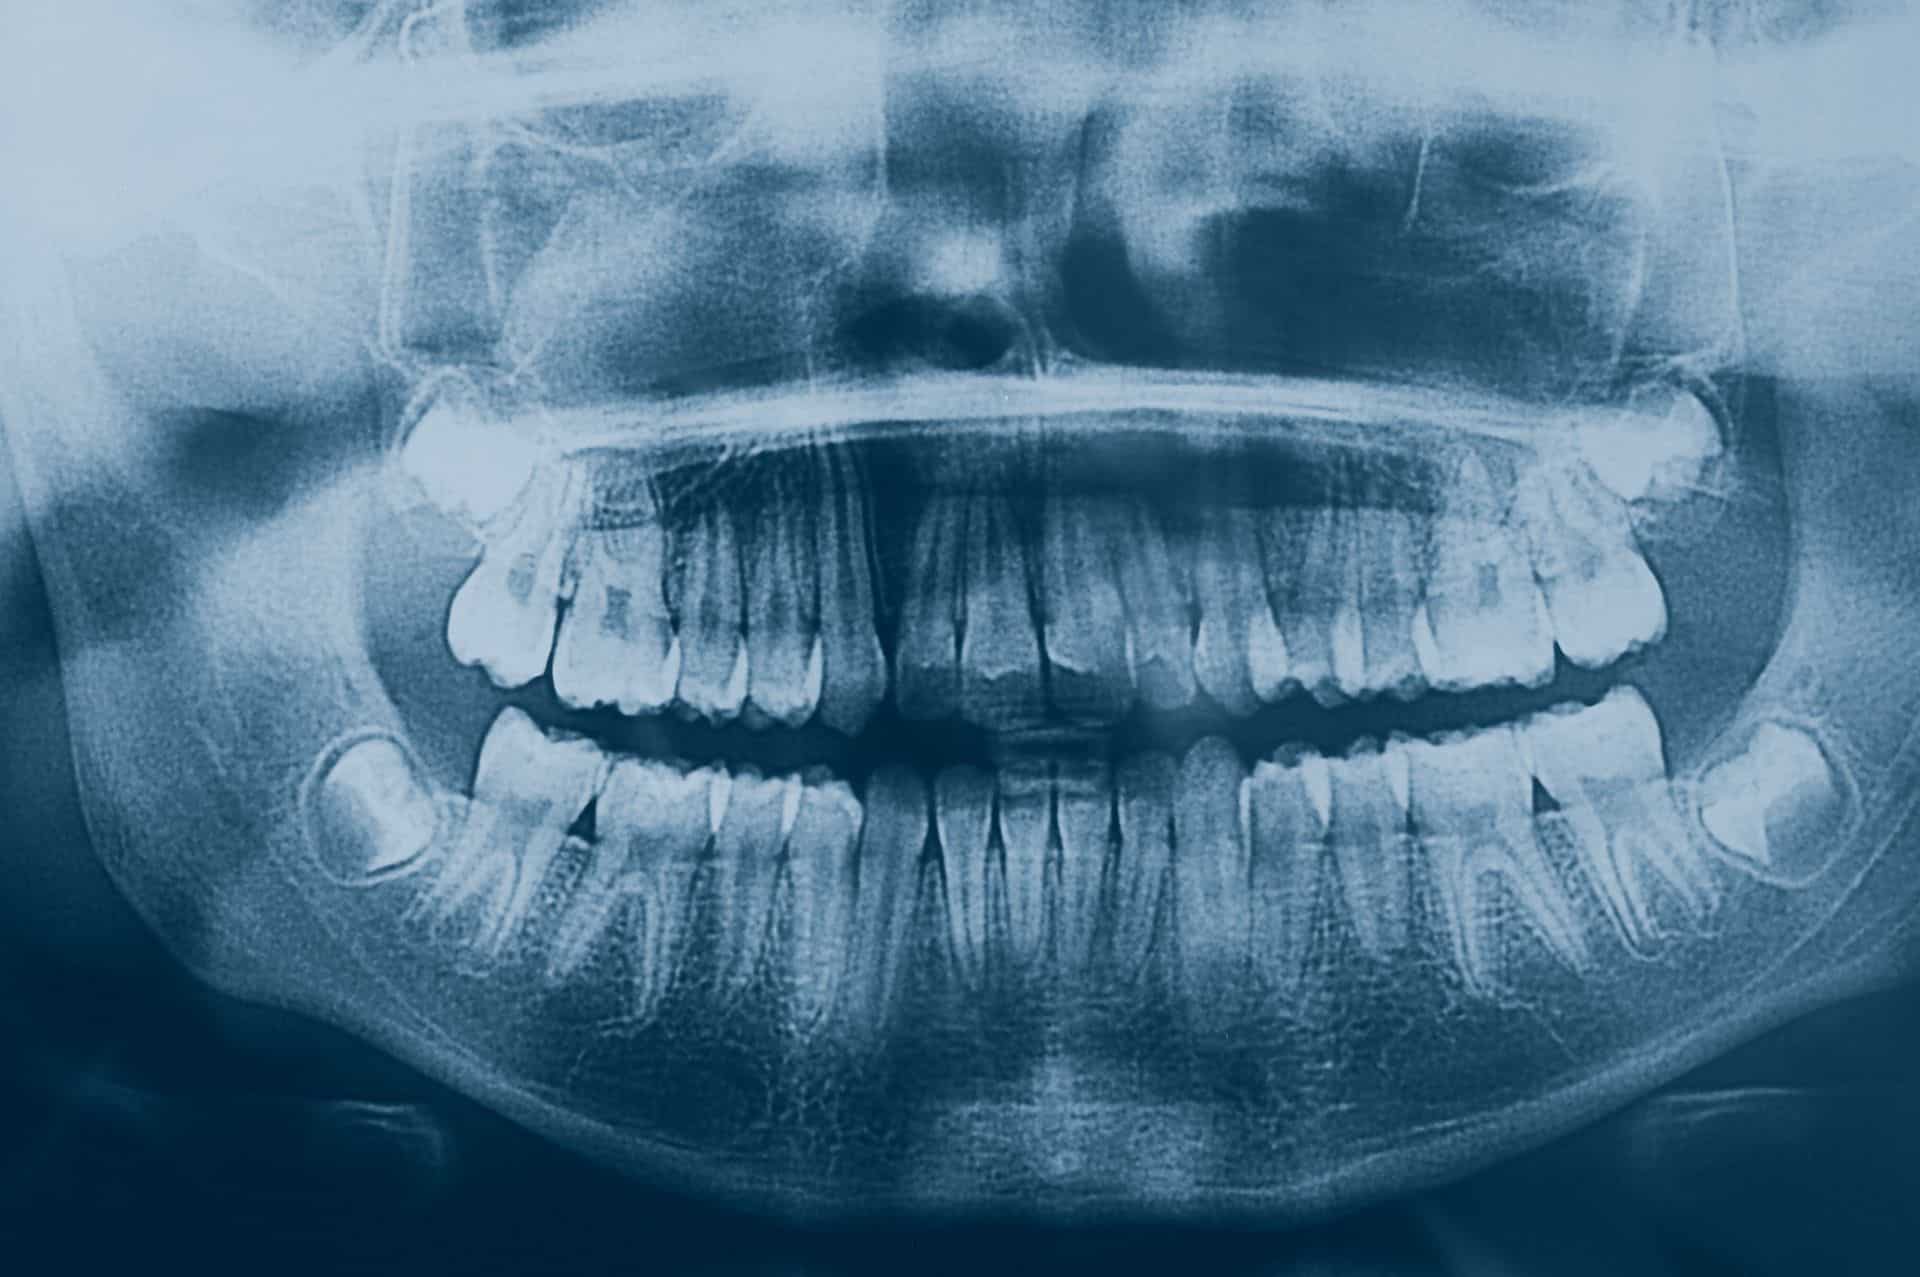

Ο εγκλεισμός ενός δοντιού μπορεί να προκληθεί από την ακατάλληλη θέση του αναπτυσσόμενου οδοντικού σπέρματος μέσα στο οστό. Αυτό μπορεί να έχει σαν αποτέλεσμα την αδυναμία ανατολής (εμφάνισης) του δοντιού στο στόμα. Ο εγκλεισμός ενός δοντιού μπορεί να προέλθει επίσης από την πρόωρη απώλεια νεογιλών δοντιών ή το συνωστισμό των δοντιών ή λόγω κάποιου άλλου εμποδίου (π.χ. οδόντωμα). Τα συχνότερα έγκλειστα δόντια είναι οι φρονιμίτες. Οι κυνόδοντες και οι προγόμφιοι μπορούν επίσης να παραμείνουν έγκλειστοι.

Συνήθως το έγκλειστο δόντι αποκαλύπτεται κατά τη διάρκεια των πρώτων μηνών της ορθοδοντικής θεραπείας και στη συνέχεια έλκεται στη σωστή θέση του στο στόμα. Η αποκάλυψη των εγκλείστων δοντιών μπορεί να απαιτεί μια μικρής έκτασης χειρουργική επέμβαση, η οποία εκτελείται από έναν στοματικό χειρούργο σε συνεννόηση με το ιατρείο μας. Αυτή η επέμβαση θα μας επιτρέψει έπειτα να φέρουμε το έγκλειστο δόντι στην κατάλληλη θέση.